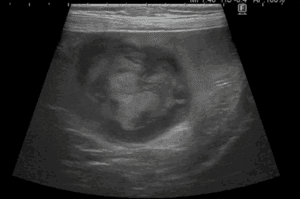

犬の副腎腫瘍は、大きく臨床症状を示す「機能性腫瘍」と、症状を示さず画像検査で偶発的に見つかる「副腎偶発腫」に分類されます。副腎は外側の皮質からコルチゾールなどのステロイドホルモンを、内側の髄質からカテコラミンと呼ばれるホ […]